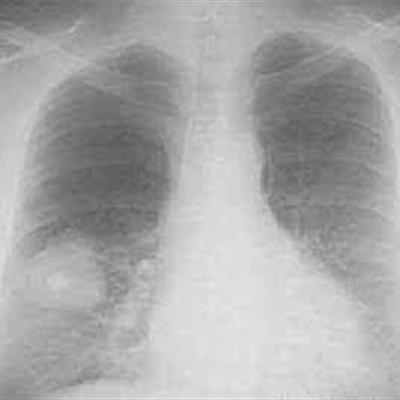

First: pneumonia is often found in children, because the child's body resistance is low, the immune system is also very weak, many times, bacteria will take advantage of the child's weak body will invade. Children are mostly caused by a cold, fever, cough, breathing difficulties. These diseases are due to children's weak immune system, causing bacterial and viral infections, bronchial dyspnea, lung infection is easy to form inflammation.

Second: Children's pneumonia as long as timely detection and effective treatment, will soon be cured. At the time of discovery or with drug treatment, take some oral antibiotics such as hydroxyampicillin, hydroxyampicillin, erythromycin is the treatment of mycoplasma pneumonia. But to prevent the recurrence of pneumonia, we still have to work hard on the rules of life and diet. This prevents children from getting sick.